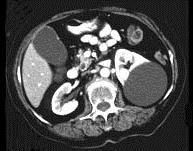

问题 女,38岁,左腰部胀痛不适,CT平扫+增强如图所示,下列说法正确的是 ( )

选项 A、考虑为左肾囊性肾癌 B、考虑为左肾囊肿 C、病灶边界清晰,表面光整 D、增强扫描皮质期和实质期该病灶均未见强化 E、平扫时可见左肾一类圆形囊性病灶

答案 BCDE